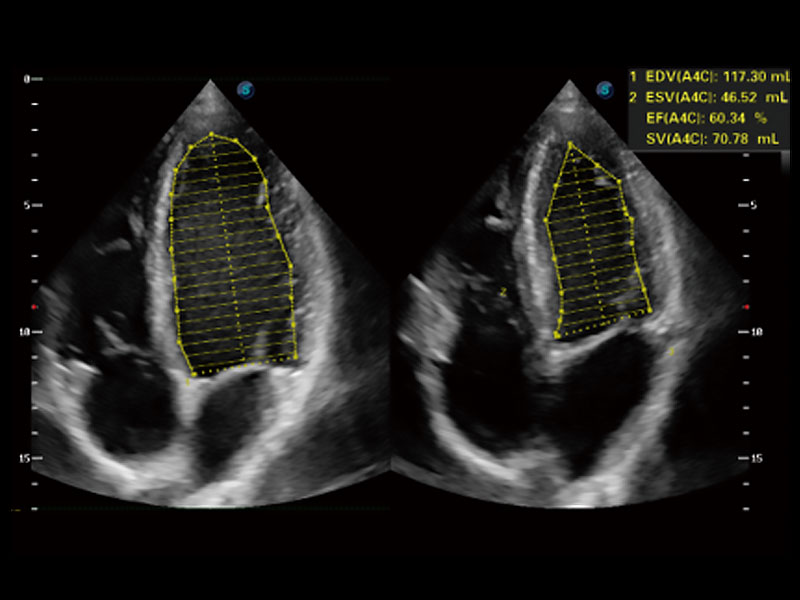

能夠基于左心室壁追蹤和辛普森法,自動計算射血分?jǐn)?shù),支持多個可移動點(diǎn)描跡,與手動測量相比,極大節(jié)省了動物醫(yī)生的時間和精力。